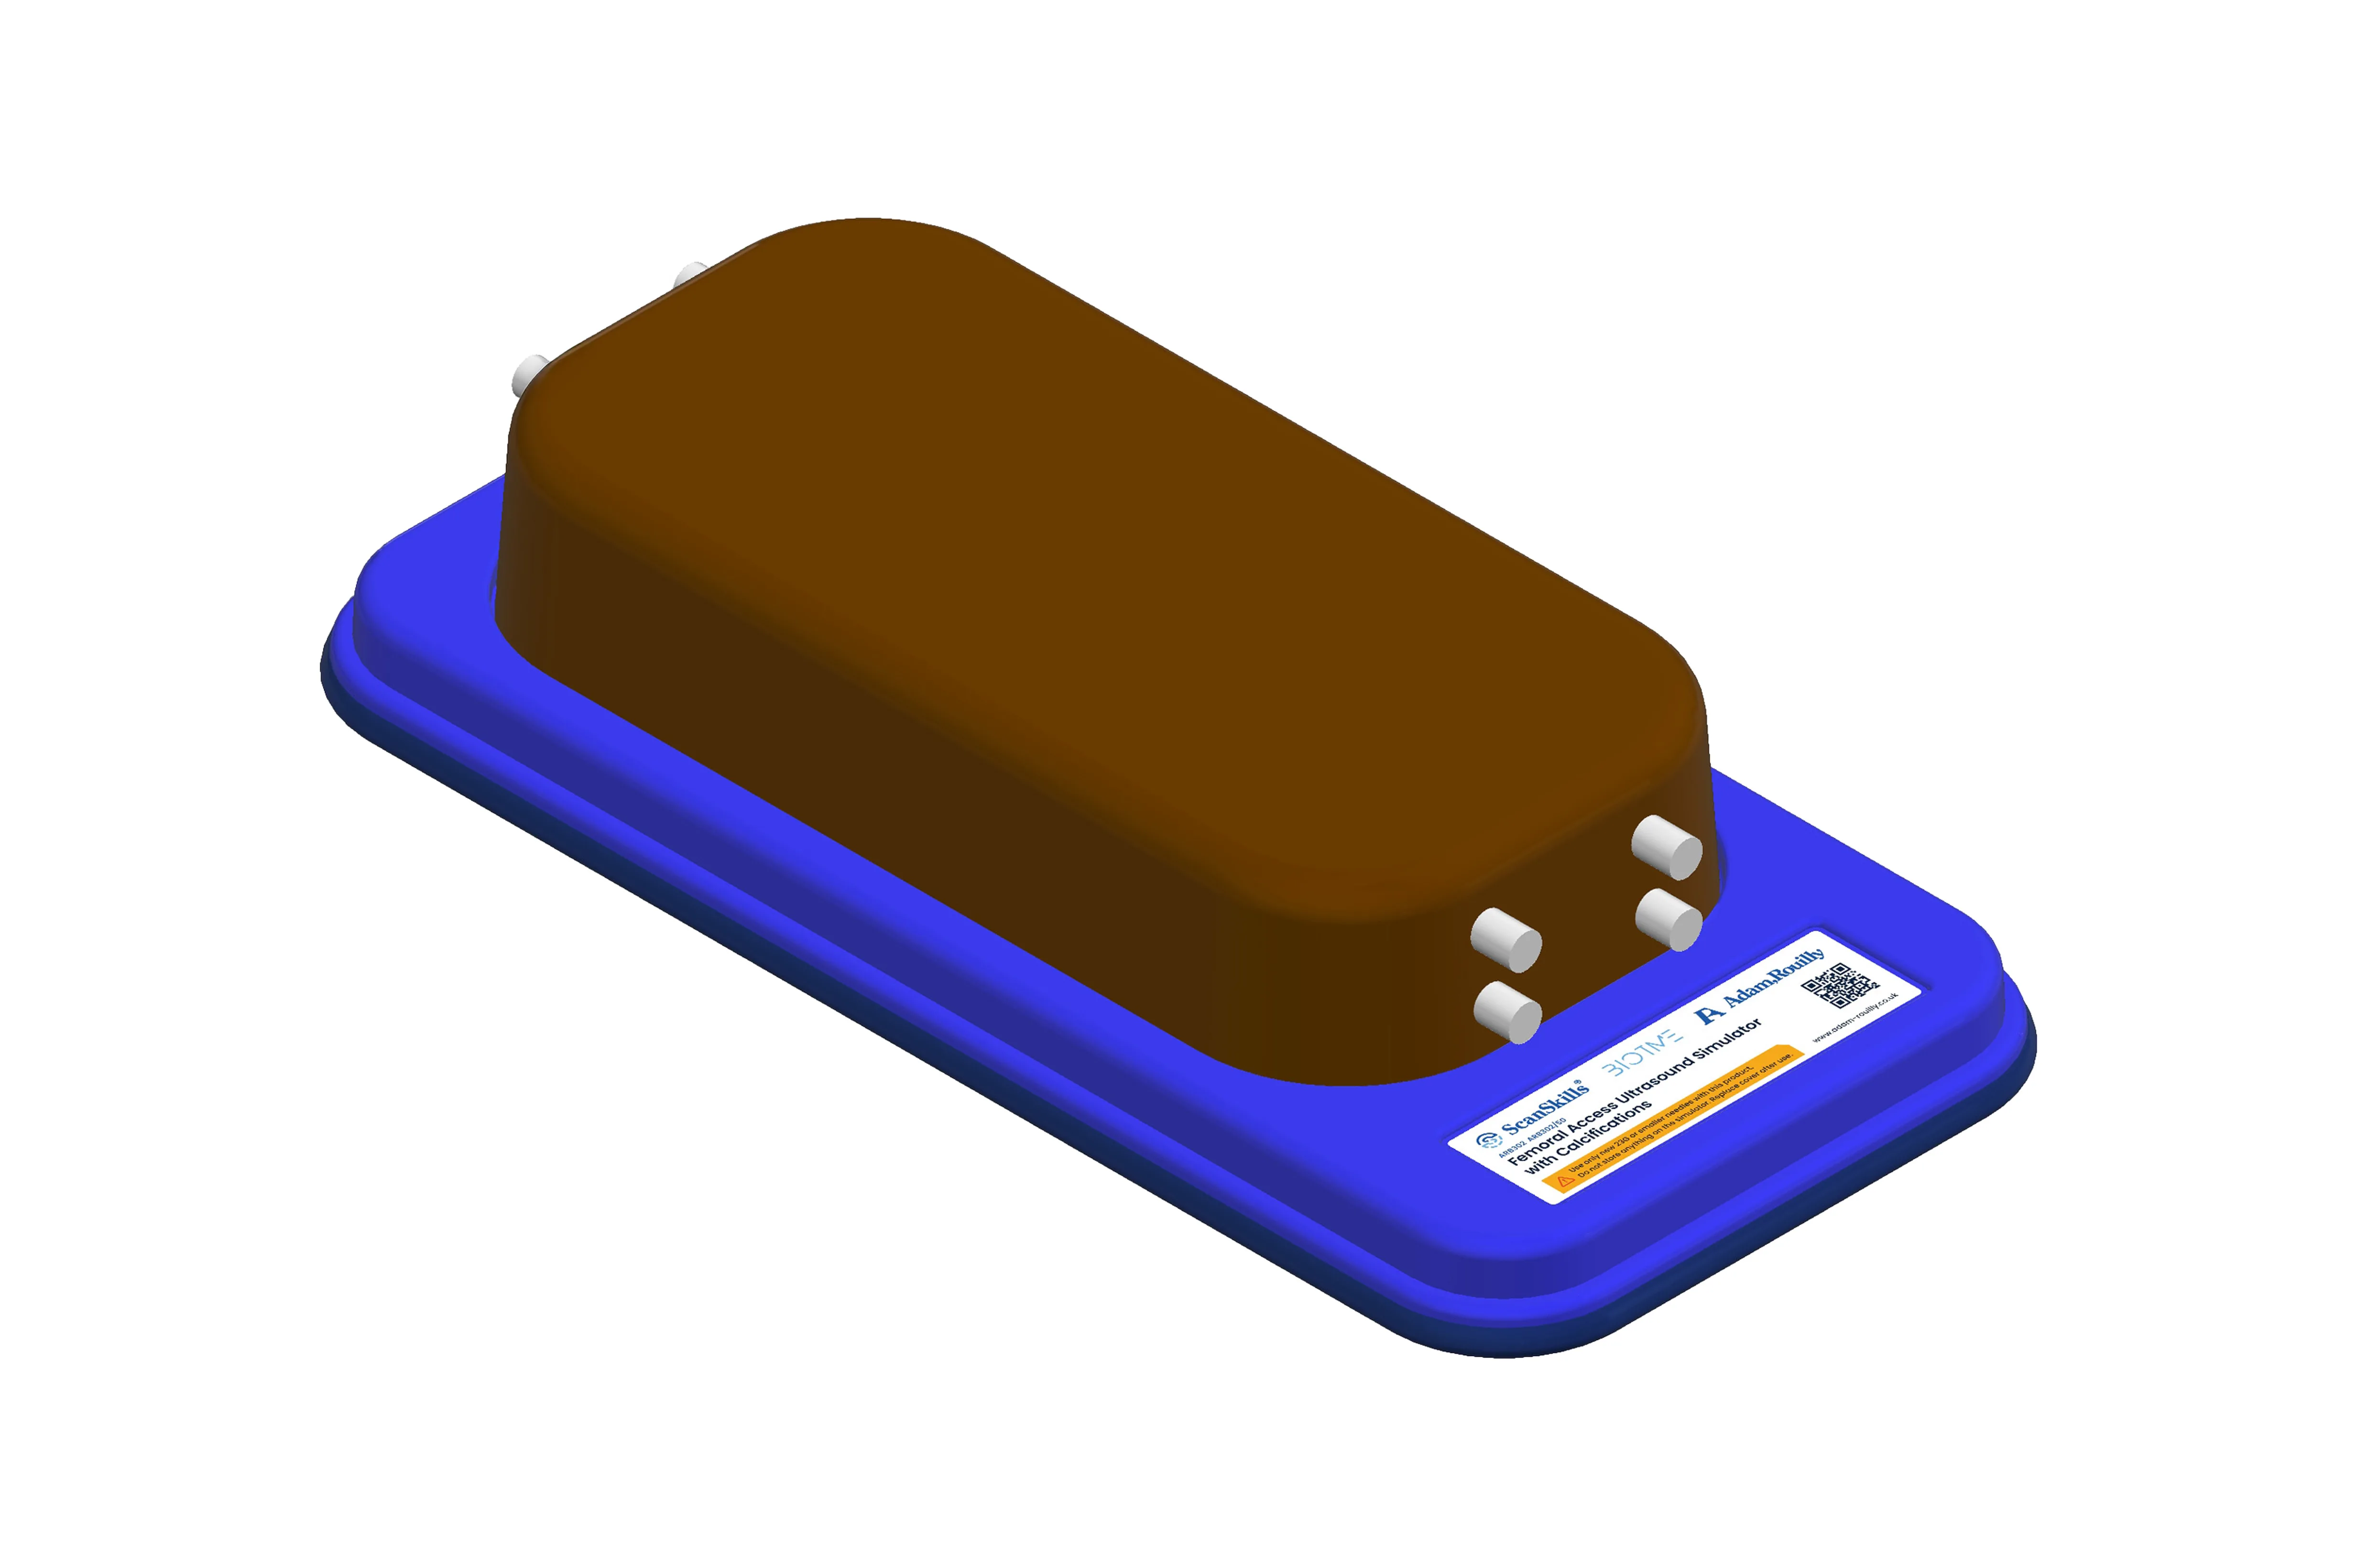

Femoral Access Ultrasound Simulator with Calcifications, Dark

Designed for femoral vascular access training, this simulator features two vertically branched veins (approx. 8 mm diameter, 20 mm deep) with simulated calcifications. Lifelike echogenic material closely mimics human tissue, enabling realistic ultrasound-guided practice, probe control, and anatomy recognition in a safe, repeatable environment for both trainees and experienced clinicians.

These products are simple, powerful training devices which allow repeated, realistic practice of ultrasound guided invasive technique. Additionally, ultrasound machine proficiency, probe dexterity and recognition of anatomical structures can be learnt – all with minimal set up and maintenance.

BIOTME are constructed from a specialist material that mimics real human tissue both in feel and in its echogenic properties. On interventional models, needle traces disappear within a few days after practice (when used with 23G or smaller needles) – enhancing both the realism and cost-effectiveness of these trainers. The materials used in the BIOTME collection are fully recyclable and can be returned to us when the time comes to replace them.

- Highly mobile all in one trainer on a base with Protective storage cover

- Size (base and lid L/W/H) 401.7, 191.5, 87.2 mm

- BIOTME ultrasound simulator mounted on a base

- Protective storage cover